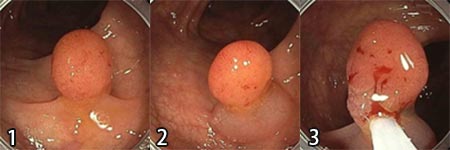

内視鏡的粘膜切除術(Endoscopic Mucosal Resection:EMR)

比較的大きな平坦なポリープに対して用いられる方法です。ポリープの下に専用のヒアルロン酸を注入しポリープを持ち上げ、その持ち上がった部分にスネア鉗子をかけ、高周波電流を流し、切除する方法です。スペースを作ることで穿孔の予防に有用です。ごく早期の大腸がんも切除できます。

- 比較的大きな平坦なポリープが対象となります(写真は10mm大のポリープ)。

- ポリープの下にヒアルロン酸液を注入してポリープを持ち上げます。

- 持ち上がった部分に鉗子をかけ、通電してポリープを切除します。